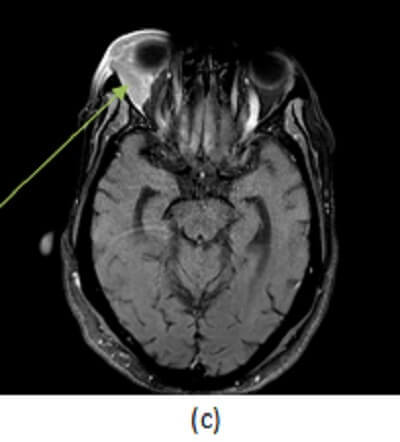

Figure 1: (a,red arrow) post contrast head CT demonstrates a smoothly marginated homogenously hyperdense extraconal mass, inseparable from the adjacent lateral rectus muscle. (b,blue arrow) Coronal T2 and (c, green arrow) axial postcontrast fat saturated T1 brain MR images in another patient with lymphoma demonstrate a tubular homogenously T2 hypointense and enhancing mass in the right lateral extraconal space that incorporates the lacrimal gland. These findings are most consistent with orbital lymphoma given the history.